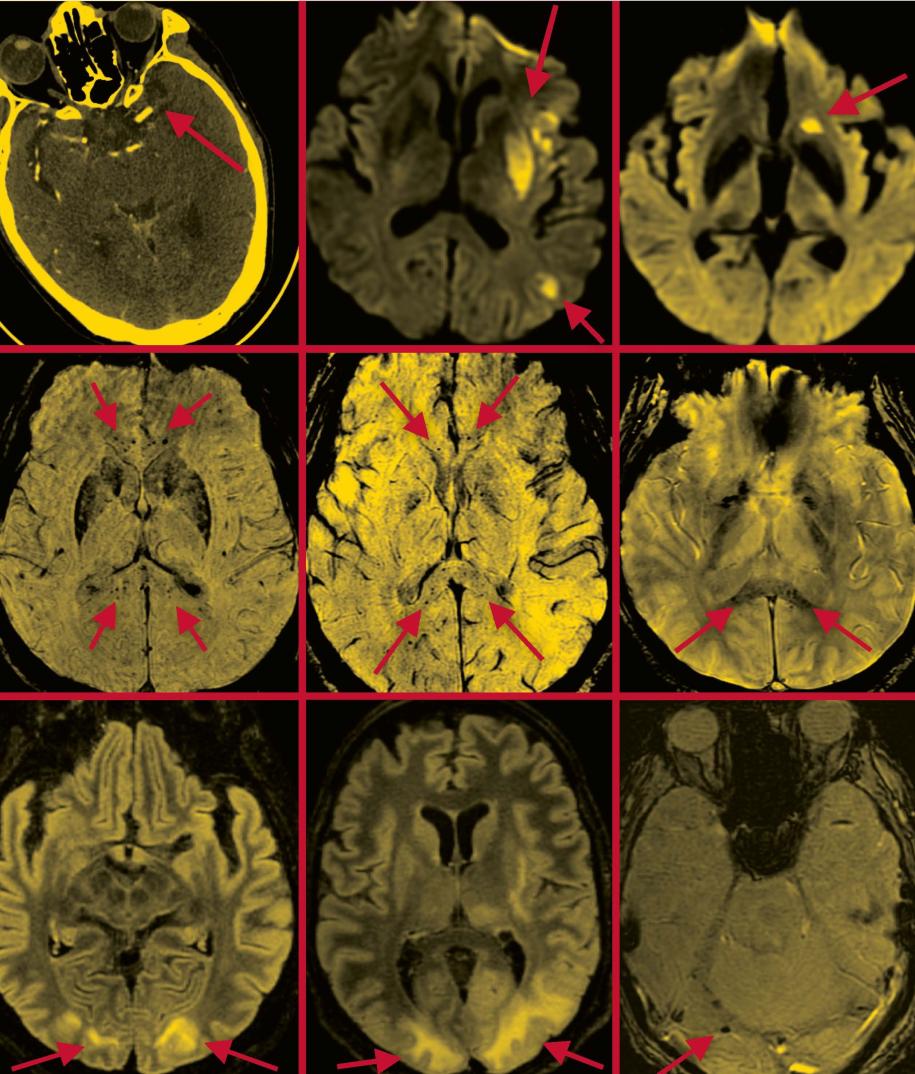

Severe Effects: Scans that appeared in a paper Dr. Navi co-authored in the American Journal of Neuroradiology depict the brains of COVID-19 patients suffering from stroke (top row); microhemorrhages in the corpus callosum region (middle row); and posterior reversible encephalopathy syndrome (bottom row), which is characterized by such symptoms as headaches, seizures, and altered mental status. Arrows in each scan indicate areas of concern. Scans provided